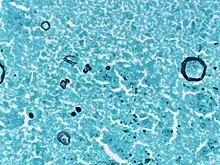

| Multiple large ruptured spherules that are devoid of endospores and are in various phases of degeneration. Free endospores are also present | |